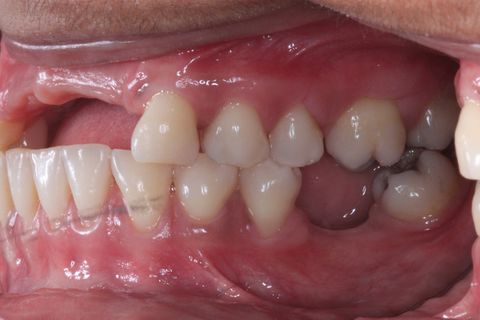

Foto Perfil (uso de espelho). Lado esquerdo

Foto Perfil (uso de espelho). Lado Direito

Foto perfil aproximada.

Foto perfil aproximada. Acentuado defeito ósseo na região vestibular